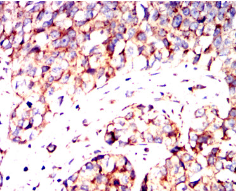

IHC    1/200 - 1/1000